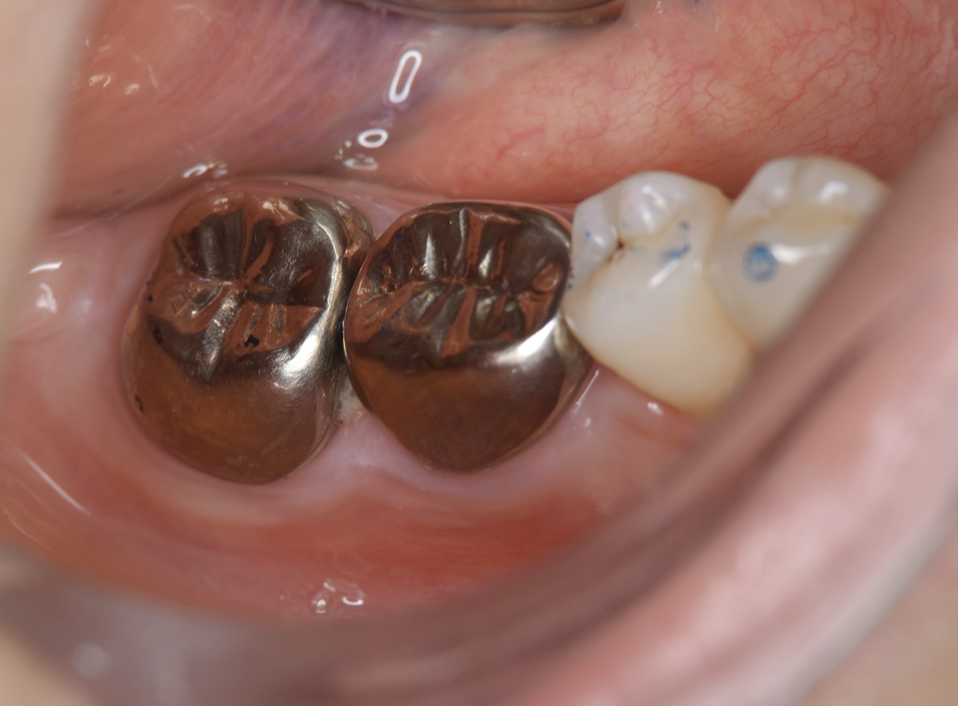

Full metal crowns were inserted for #46 and #47. Pathological mobility and bleeding on probing were not seen, and the transplanted tooth showed good function.

Endodontic treatment was initiated at 14 days after transplantation (8, 17). Root canal treatment for #48 was performed using Ni-Ti files (Pro Taper Next, Dentsply Sirona, Tokyo, Japan) to accommodate the complex morphology of the root canal and for minimal removal of the tooth structure during formation of the access cavity. Root canals were medicated with calcium hydroxide paste and then filled with gutta percha. The splint was also removed four weeks after the operation and a resin core was used as an abutment construction. In an attempt to appropriately modify contact and the crown morphology, a crown prosthesis was made with a full metal crown, with occlusal contact confirmed with use of a temporary crown and easy to visualize markings on occlusal paper. The full metal crown was cemented six months later (Figure 7).

Bone regeneration was confirmed before and after grafting, after root filling, and after placement of the prosthesis, based on X-ray imaging results (Figure 8). There was no pathologic mobility or pain during mastication, and the tooth showed good function. The patient was very satisfied with the treatment results (Figure 9).

Figure 7.Inter-oral photo obtained after treatment. Full metal crowns were inserted for #46, #47. Pathological mobility and bleeding on probing were not seen, and the transplanted tooth showed good function.